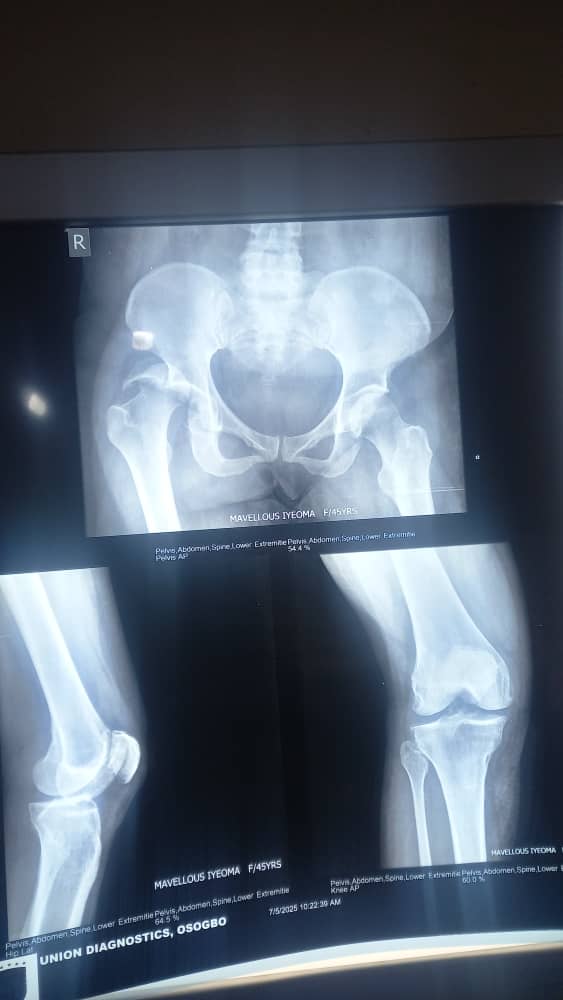

Four months after the ghastly accident, Ifeoma is stuck in a wheelchair and needs N3.5m to undergo a final stage of corrective surgery at Asala Bone Centre in Osogbo.

“The first hospital where I was rushed to and then admitted was LAUTECH in Ogbomosho. I was later transferred to Asala Specialist Bone Centre, a private hospital in Osogbo, where I had the first stage of surgery.

He told Sports247: “She was our regular left-full-back in the CATS Girls’ team, up until the time we disbanded all the squads in 2009. I am still in shock to hear her story and see such scary photographs of her current condition.